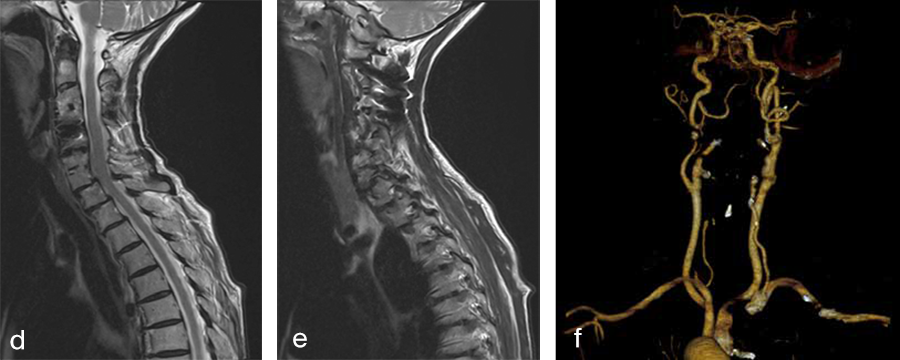

Her preoperative radiographic evaluation comprised x-rays, functional x-rays, computed tomographic, and magnetic resonance imaging scans (Fig 4) and demonstrated:

Preoperative imaging (Fig 4a-f), showing:

- C2-C4 posterior instrumentation and fusion.

- Anterior fusion after Anterior Cervical Decompression and Fusion (ACDF) C3/4 and C6/7.

- Status after total disc replacement of C4/5 with heterotopic ossifications.

- Nonunion C5/6 after ACDF C5/6.

- Spondylolisthesis C7/Th1 with neuroforaminal stenosis on both sides.

- A normal cervical angiogram (cave: artefacts).